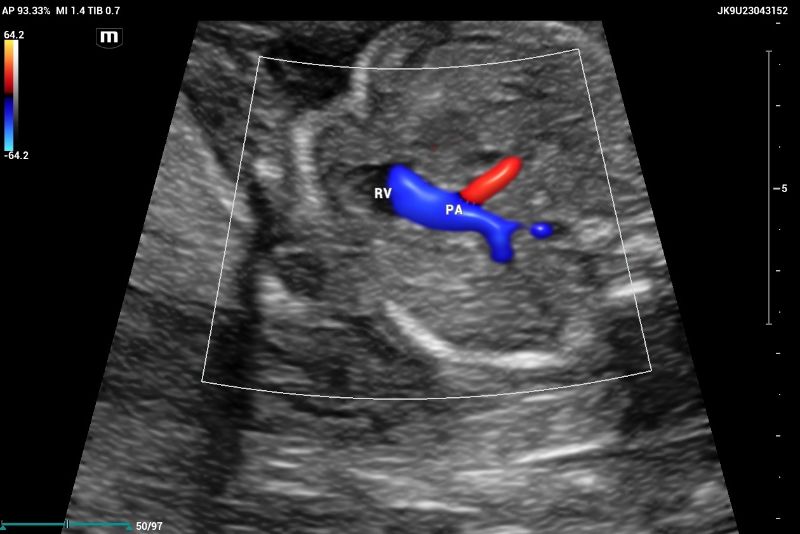

Outflow tract of aortic and pulmonary arteries and functional evaluation (Figure 4-6).

Example of normal echocardiography performed on Mindray Resona I9 system. Artery – ventricle concordance outflow tract showing pulmonary artery (PA) emerging of the right ventricle (RV)

Figure 4. Example of normal echocardiography performed on Mindray Resona I9 system. Artery – ventricle concordance outflow tract showing pulmonary artery (PA) emerging of the right ventricle (RV)